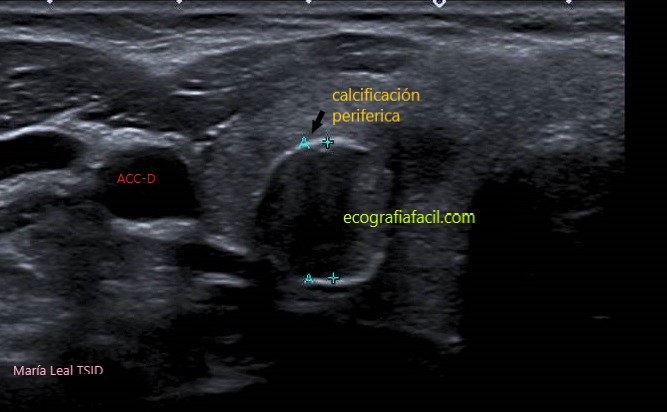

CALCIFICACIÓN PERIFÉRICA: